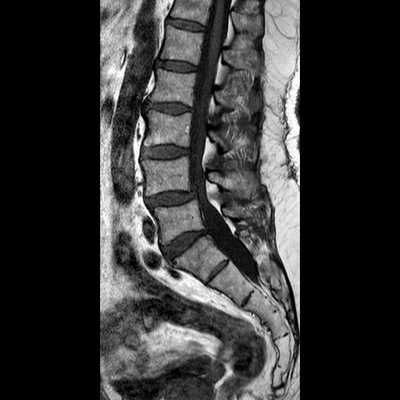

МРТ позвоночника. Сагиттальная Т2-взвешенная МРТ, срединный срез поясничного отдела. Показана нумерация позвонков, измерения позвоночного канала (черная линия). Т- дуральный мешок с ярким ликвором. L- желтая связка. Sacrum - крестец. D - межпозвоночный диск. Голубым выделен остистый отросток, желтым - тело позвонка, Голубые точки - ход корешков.

МРТ позвоночника. Парасагиттальная (околосрединная) Т2-взвешенная МРТ поясничного отдела. Красными стрелками показаны корешки.